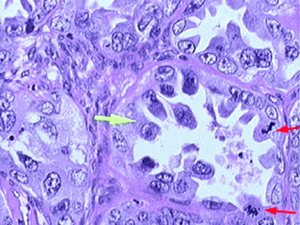

Clear cell carcinoma of the ovary

In the third study analysis, the researchers used immunohistochemical analysis (IHC) to measure BAF250a protein expression in 450 ovarian cancers.

The first round of IHC testing involved 182 ovarian cancers which were available from the discovery cohorts and the mutation-validation cohorts: 73 OCCCs, 33 endometrioid cancers, and 76 high-grade serous ovarian cancers. The goal of the first IHC analysis was to compare the loss of BAF250a protein expression in OCCCs and endometrioid cancers, with and without ARID1A mutations. Upon completion, the researchers identified loss of BAF250a protein expression in 27 of 37 (73%) OCCCs, and 5 of 10 (50%) endometrioid cancers, which possessed ARID1A mutations. In contrast, loss of BAF250a protein expression was identified in only 4 of 36 (11%) OCCCs, and 2 of 23 (9%) endometrioid cancers, which did not possess ARID1A mutations. Thus, the loss of BAF250a protein expression was much greater in OCCCs and endometrioid cancers with ARID1A mutations.

The goal of the second IHC analysis was to compare loss of BAF250a protein expression among all OCCCs, endometrioid cancers, and high-grade serous cancers. The researchers identified loss of BAF250a protein expression in 31 of 73 (42%) OCCCs, and 7 of 33 (21%) endometrioid cancers, as compared to 1 of 76 (1%) high-grade serous cancers. Thus, the loss of BAF250a protein expression was much greater in the OCCCs and endometrioid cancers, as compared to high-grade serous cancers, regardless of ARID1A mutation status.

The second round of IHC testing measured loss of BAF250a protein expression within the IHC validation cohort. This analysis revealed that 55 of 132 (42%) OCCCs, 39 of 125 (31%) endometrioid cancers, and 12 of 198 (6%) high-grade serous cancers, lost BAF250a protein expression.

By the end of IHC testing, the researchers established that the loss of BAF250a protein expression was consistently more common in OCCCs and endometrioid cancers than in high-grade serous cancers, when assessed in the discovery and mutation-validation cohorts, and again in the IHC cohort.